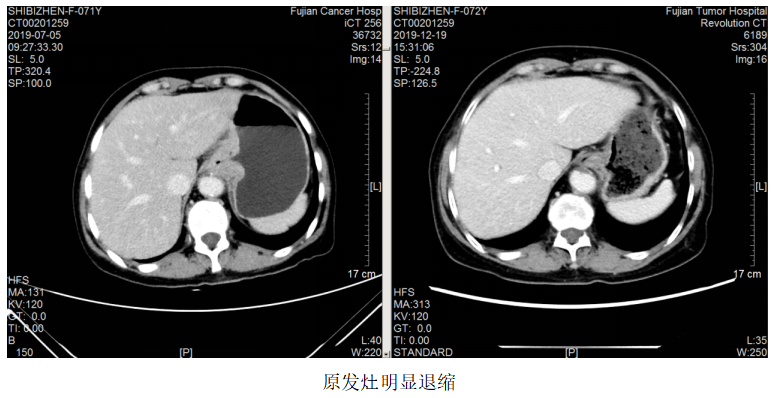

图1.2019.7.5影像(基线评估)

一线治疗:2019.7.12~10.24予FOLFOX方案(奥沙利铂110mg+左亚叶酸钙300mg+5-Fu 2.75)化疗8周期,曲妥珠单抗220mg靶向治疗7次。

疗效评估:PR。